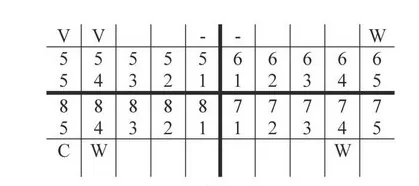

Instrumentem przedstawionym na ilustracji stosowanym w chirurgii stomatologicznej jest

| 1 | 1 | 1 |

| 17-14 | 13-23 | 24-27 |

| 47-44 | 43-33 | 34-37 |

| 1 | 3 | 1 |